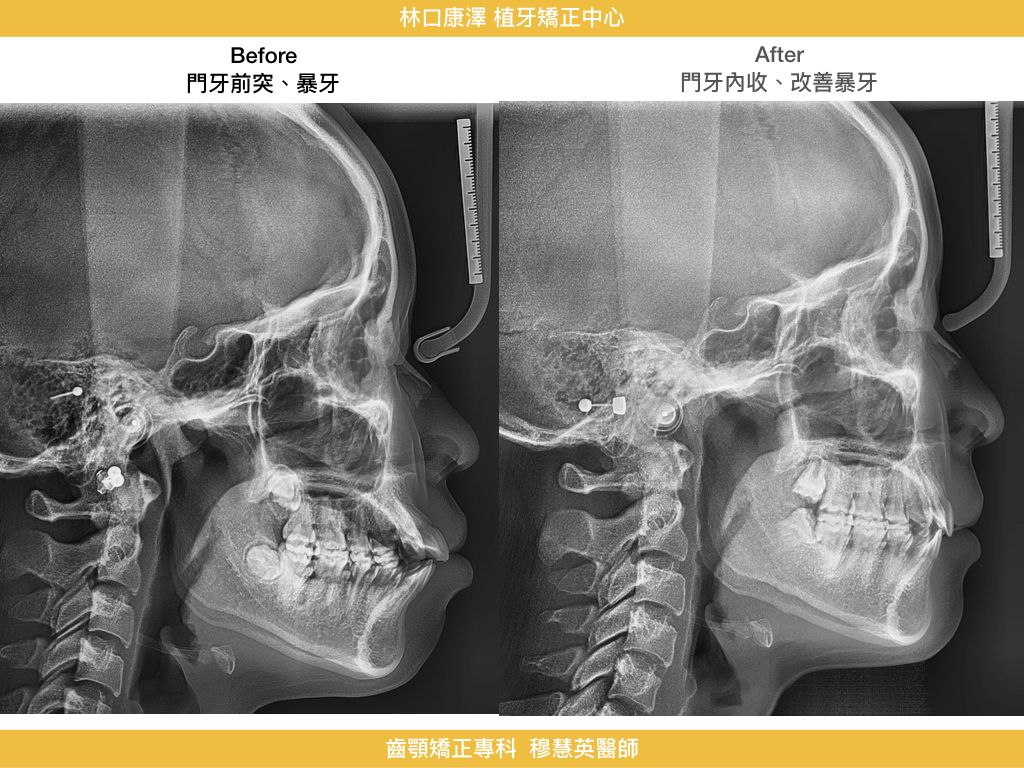

【暴牙與口唇閉合困難的改善】

改善暴牙、嘴唇閉合困難與臉型突出,找回柔和側臉與自信笑容!

這是一個改善外觀的經典矯正案例,在康澤牙醫由矯正專科穆慧英醫師治療下,透過拔牙空間內收前牙,不只處理了牙齒排列,更徹底解決了唇形與臉型比例的長期困擾。成年女性在意的,不只是矯正後的牙齒整齊,而是從正面到側面,每一個角度都能展現自信與自然美感。

- 門牙順利內收:前突狀況明顯改善,口唇不再外翻

- 嘴唇可自然閉合:靜態時不再緊繃,表情更放鬆柔和

- 側臉輪廓變直:由原本的凸面型轉為柔和直線型,臉型更協調